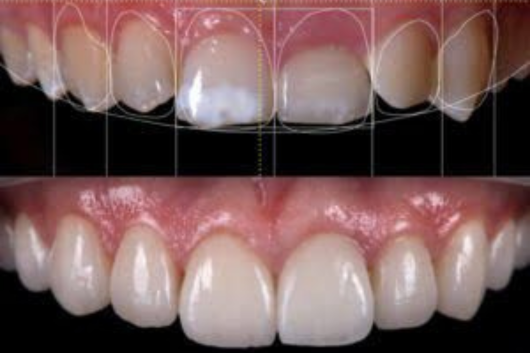

Smile designing & tooth jewellery

Smile designing is a customized approach to align your teeth and enhance your overall smile. Since every smile is unique, the process is tailored to your facial structure and dental concerns. Whether it’s crooked, stained, yellowed, or misaligned teeth, smile designing helps correct imperfections for a confident smile. The procedure involves evaluating your current smile, treating the gums, and restoring tooth color — making it a comprehensive transformation journey.